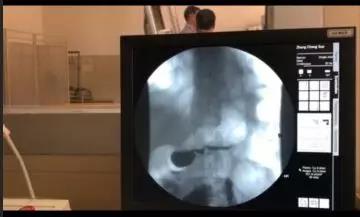

患者術(shù)后行上消化道造影檢查顯示:吻合口通暢,平臥位甚至頭低30°無(wú)明顯反流。

在過(guò)去的20年里,近端胃癌的發(fā)病率顯著升高。為了保留部分胃功能,減少營(yíng)養(yǎng)性并發(fā)癥,很多醫(yī)院采用近端胃切除。但與全胃切除相比,近端胃切除易出現(xiàn)反流性食管炎和吻合口狹窄等并發(fā)癥。目前,近端胃切除后消化道重建方式主要包括食管胃吻合(Esophagogastrostomy,EG )、間置空腸(jejunal interposition,JI)和雙通道重建(double tract reconstruction,DTR )。腹腔鏡下近端胃切除食管胃Kamikawa吻合技術(shù),與上述3種吻合方式比較,食管胃吻合口處肌瓣包裹重建,相當(dāng)于"再造賁門" ,減少反流性食管炎發(fā)生。同時(shí),利用胃前壁漿肌瓣覆蓋吻合口,降低了吻合口瘺?;颊咝g(shù)后恢復(fù)快、進(jìn)食早、吞咽通暢、無(wú)反流等不適,術(shù)后消化道造影提示“吻合口通暢,無(wú)明顯反流”。該術(shù)式具有很好的臨床應(yīng)用前景。